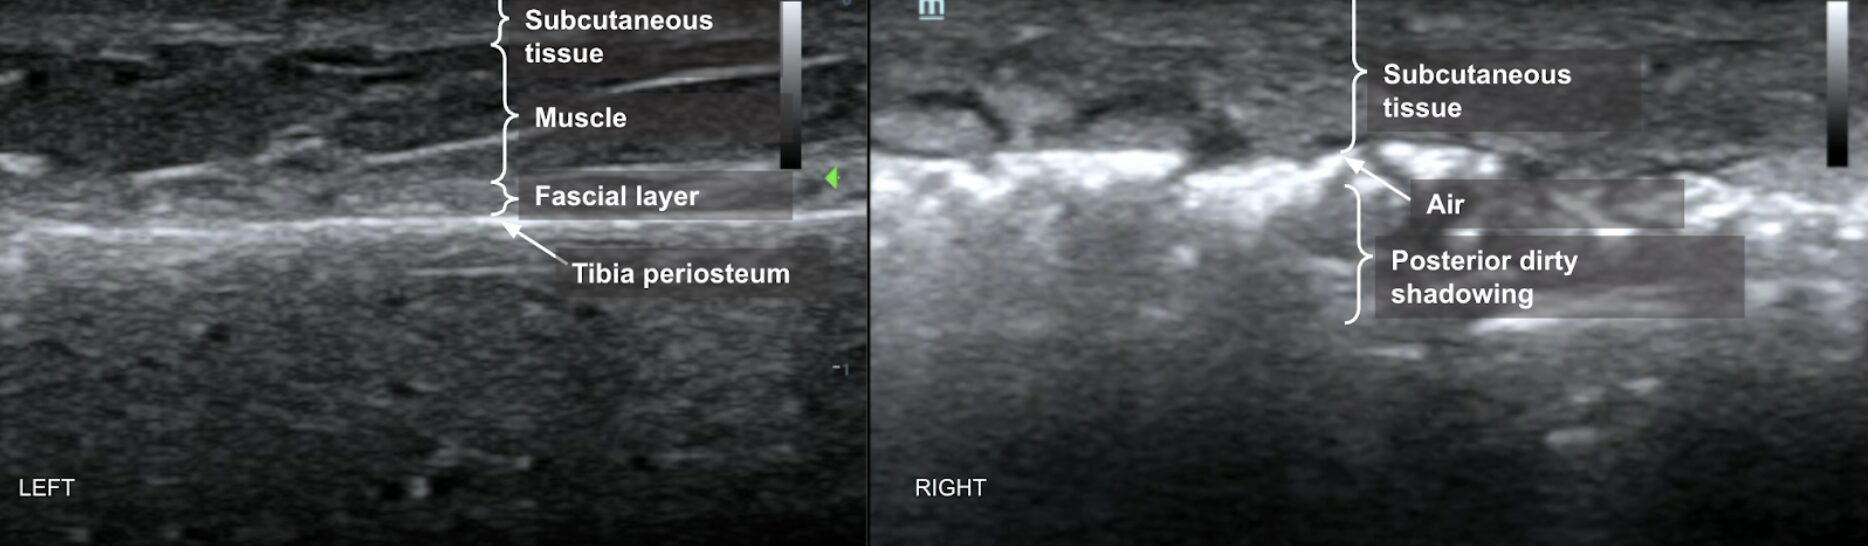

Subcutaneous thickening refers to the widening of the subcutaneous layers. It often occurs with notable edematous infiltration in the form of anechoic streaking between isoechoic dermal layers on POCUS. Classifying the area of interest as abnormal can be established by comparing the affected region of concern to nearby unaffected tissue or to an unaffected contralateral limb (Image 1). This disruption of normal subcutaneous architecture can also demonstrate the finding of “cobblestoning” typically seen in cellulitis or edema. This finding occurs due to the presence of volume overload, inflammation, or infection.

Subcutaneous emphysema on POCUS is demonstrated by hyperechoic foci with posterior “dirty shadowing” in the subcutaneous tissues. Since air scatters ultrasound beams, it results in a heterogeneous, speckled shadowing deep to the gas (Image 1, Image 2, Video 1).3 While subcutaneous emphysema is a key finding of necrotizing soft tissue infection (NSTI), it is also important to remember that it may be present in situations where there was dermal puncture that would introduce air into the soft tissue, such as in the case of animal bites or in the case of actively draining abscesses. In such clinical examples, subcutaneous air alone may not suffice to seal the diagnosis of NSTI.

Image 1:

LEFT: POCUS of unaffected lower leg using the linear transducer. Normal skin, subcutaneous layers, and muscle architecture are maintained.

RIGHT: POCUS of affected lower leg using the linear transducer. Thickened subcutaneous tissue, disruption of subcutaneous architecture, anechoic streaking, and some notable cobble-stoning in deeper fields are noted. Note also the presence of air with posterior dirty shadowing obscuring underlying muscle and bone. Images courtesy of Dr. Shepherd and Dr. Alerhand.